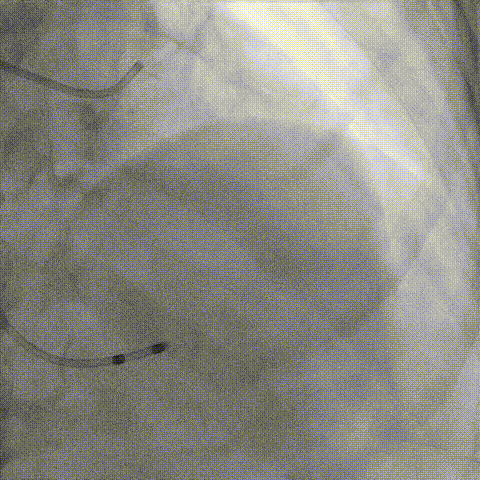

Telescope™+Runthrough

18mm*40mm 预扩张

预埋 Resolute Integrity 3.5*26mm

再次评估左冠开口